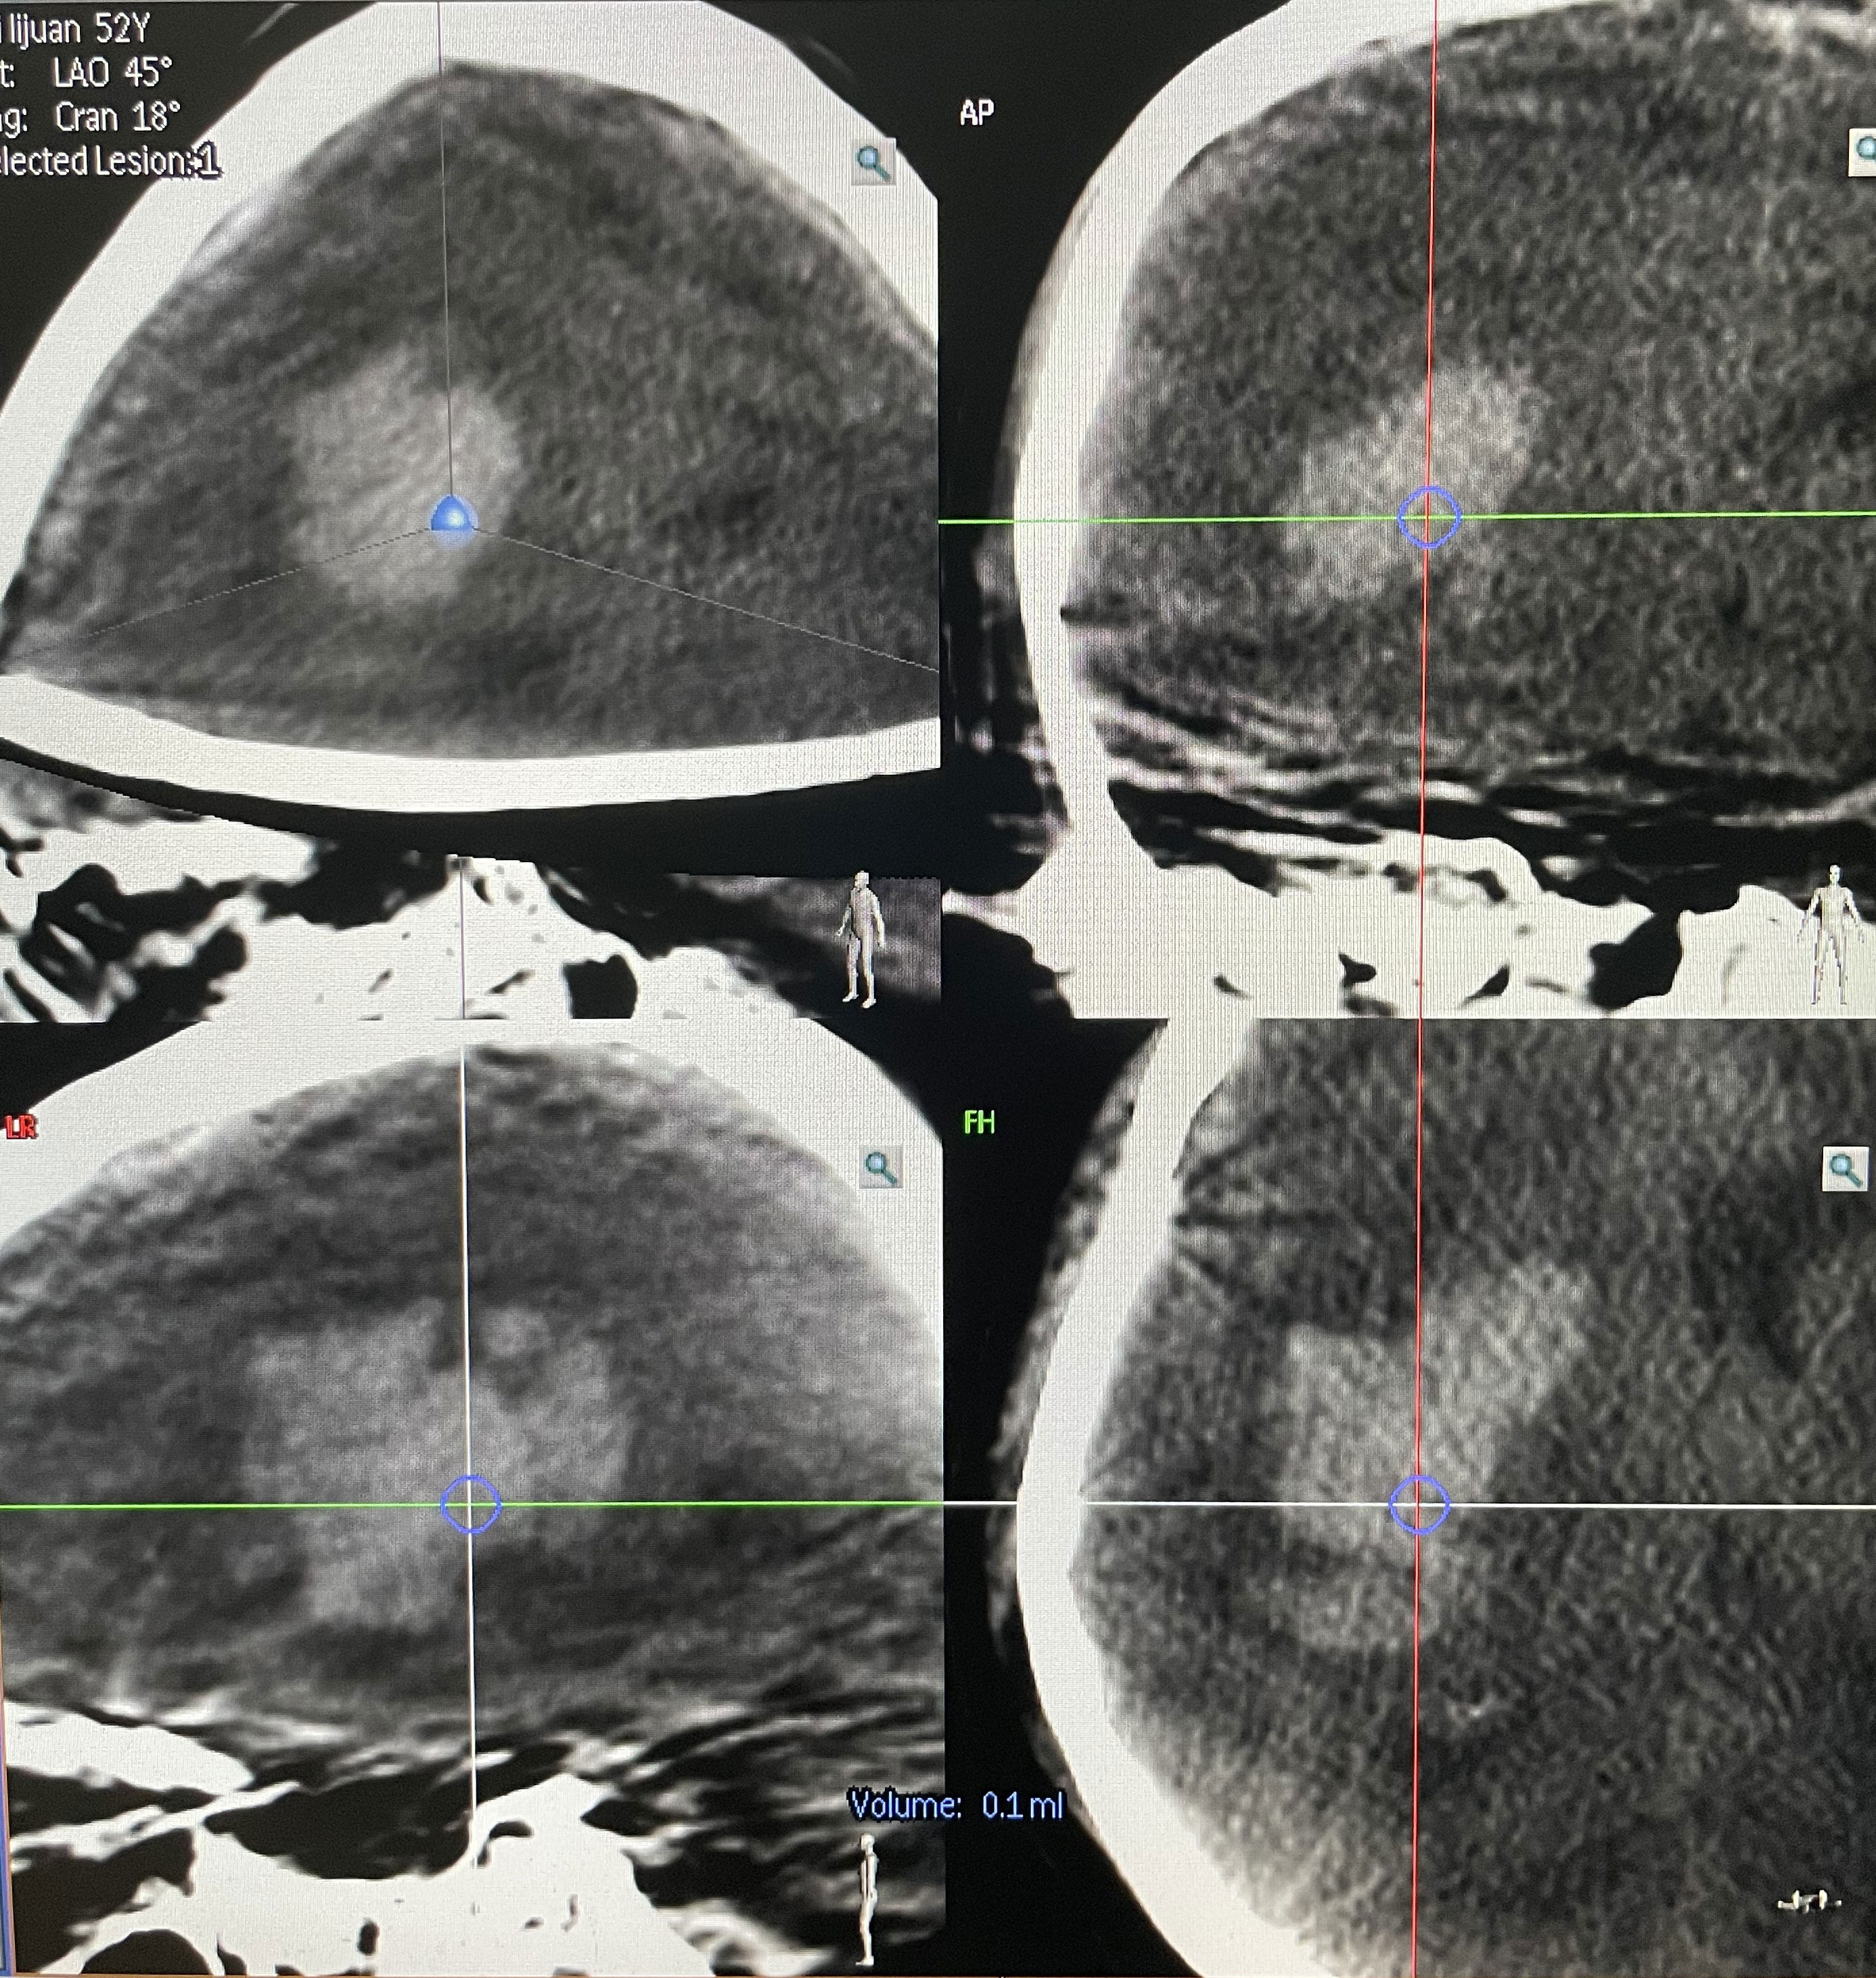

The surgical incision site was marked with a metal object on the forehead, approximately 2 cm from the midline and 3 cm from the orbit on the hematoma side (Figure 2). The priority was to make an incision in the frontal stria and avoid the frontal sinus to prevent cerebrospinal fluid leakage after surgery and ensure an aesthetically pleasing appearance after wound healing. A hole was drilled in the bone at the metal mark (Figure 3). The C-arm CT function of the digital subtraction angiography (DSA) machine was used to collect the original data for processing; display the coronal, sagittal, and axial CT images; mark the center of the hematoma; and set it as the target site for the puncture (Figure 4). The 3D reconstruction of brain tissue was performed using the 3D reconstruction software Xper CT of the DSA machine, and the bone hole displayed in gray scale was adjusted as the puncture point. Subsequently, the 3D stereo image was rotated, overlapping the puncture point and puncture target. The laser emission direction was determined using the principle of “two points and one line,” and the real-time 3D reference image working angle was recorded (Figure 5). The skull was cut along the coinciding point, and the distance between the puncture point and the puncture target was measured as the puncture depth (Figure 6).

The 3D APC function was used in the Xper APC automatic position control module to automatically position the rack movement to the angle displayed by the 3D reference image (Figure 7) (9).